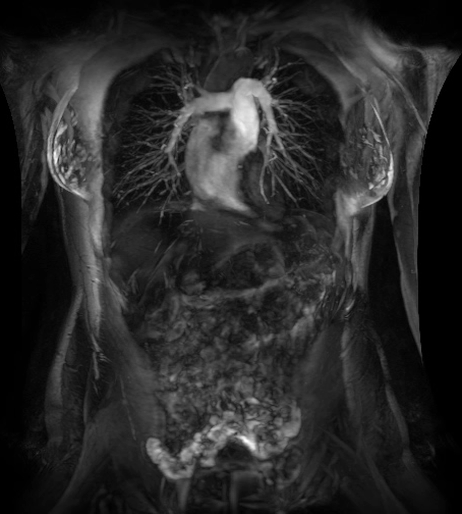

在乳腺MR檢查中,SIGNAWorks?通過可調(diào)節(jié)線圈元件使得乳腺成像實現(xiàn)定量化和個性化,從而實現(xiàn)精準(zhǔn)醫(yī)療。創(chuàng)新型應(yīng)用——用于超快速動態(tài)掃描的DISCO,用于高分辨率形態(tài)成像的Cube T2 with HyperSense和Cube T2 HyperCube,縮短了掃描時間并促進(jìn)了擴(kuò)散技術(shù)(Focus和MUSE)的發(fā)展,利用與BIRADs一致的CADStream來探測組織特征和分析。